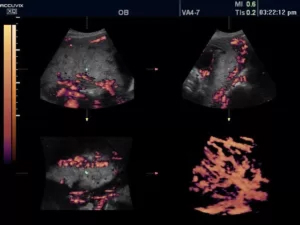

21.jpg

Рис.2. Почка в режимах CFI и PW.

Режим CFI (Color Doppler Imaging, ЦДК, цветовое допплеровское картирование)

Цветовой доплеровский режим позволяет анализировать характеристики кровотока не только в формате графика на осях, но и в виде цветной схемы. На ней красным цветом выделяются потоки крови, идущие по направлению к датчику, а синим — в противоположную от него сторону. Насыщенность оттенка свидетельствует о скорости движения эритроцитов: чем она ниже, тем ярче изображение.

23.jpg

Рис.3. Пуповина плода в режиме ЦДК + LumiFlow (программное обеспечение, устанавливаемое в ультразвуковом аппарате высокого разрешения).

Поскольку исследование в режиме CFI на большой области обладает ограниченной информативностью, спектральная доплерография предоставляет более детальные данные о небольшом участке, оба режима дополняют друг друга и в практической работе применяются совместно.